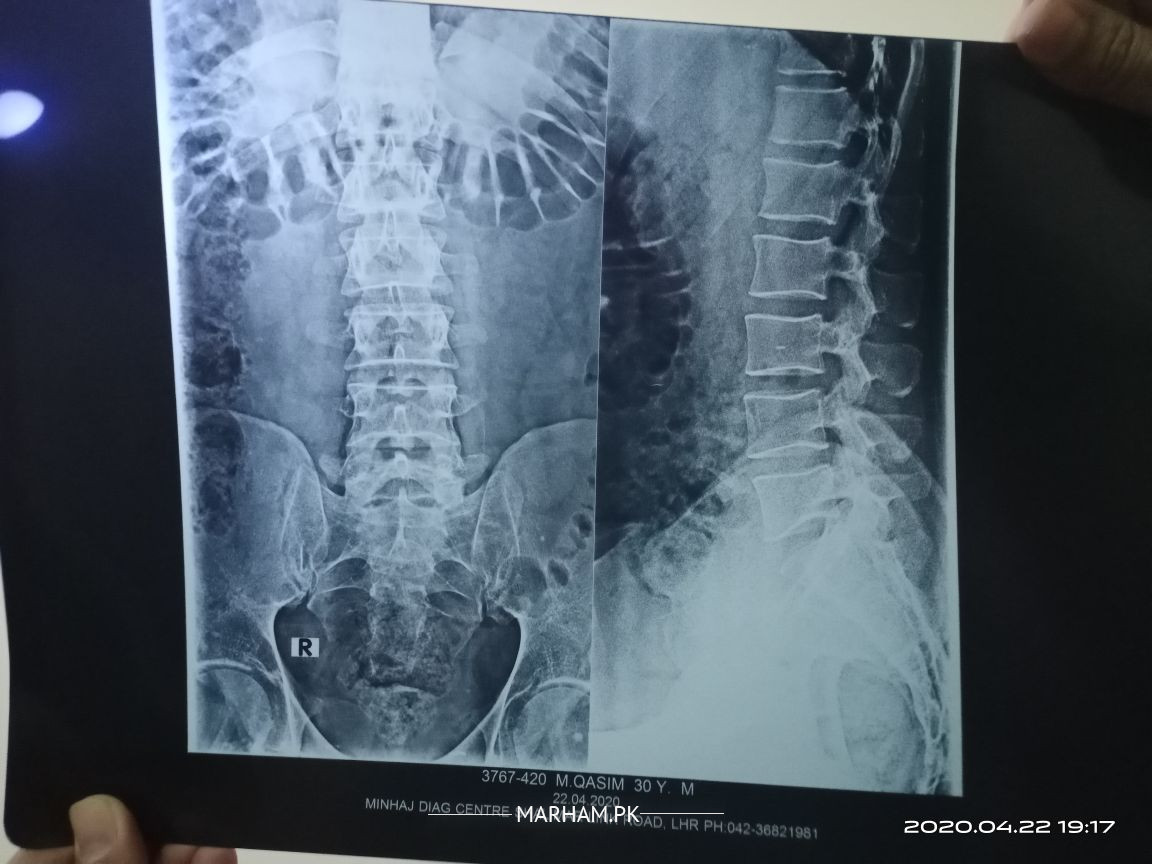

plz see attached xray and suggest. i am feeling pain in lower back and hip joints. its been a week now.

xray looks fine?

xrays looks fine. u need proper assessment . till that plz start tab Myolax 4mg BD

There is degenerative changes and loss of lumbar lordosis on X-rays. For proper treatment u need physical assessment. Meanwhile use painkillers and do physiotheraphy. If no improvement visit spine surgeon nearby.

Hi, you have to give complete history of the problem. Your xray is normal looking. You need to be examined by orthopaedic surgeon. Thanks